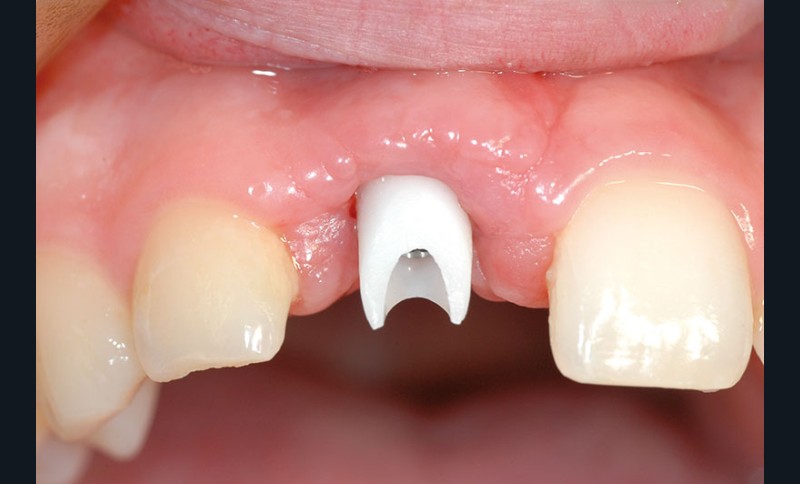

Nous proposons de retirer la couronne et le pilier implantaire, d’effectuer une greffe de tissu conjonctif enfouie afin d’améliorer le volume du tissu kératinisé péri-implantaire [5] et de procéder à la pose d’une couronne provisoire transvissée (fig. 3a à h).